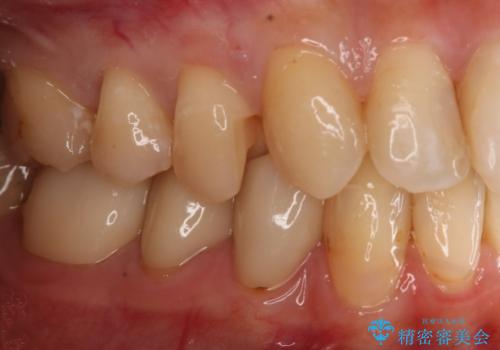

変色した詰め物の再治療 セラミックインレー

- 以前保険で治療した詰め物の変色を治したいとの主訴でご来院されました。

審美性と耐久性に優れたセラミックインレーで治療しました。

セラミックは素材の色調が歯に近く経年的な変色もないため、長期の審美性維持が可能となります。